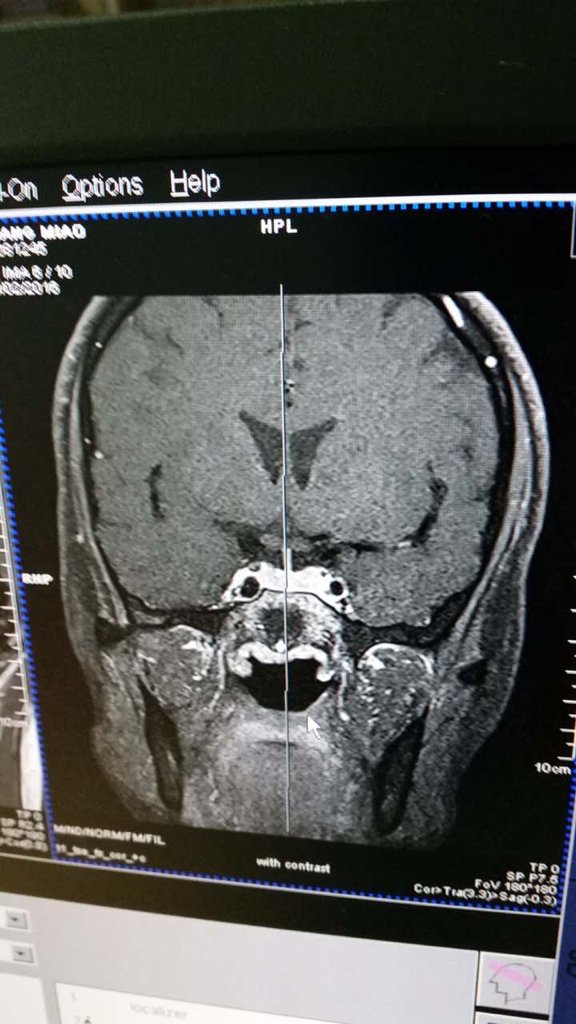

我28岁,未婚未育但因为月经不调,泌乳素200,于是做了垂体磁共振,麻烦懂的医生看看这片子里有没有

我28岁,未婚未育但因为月经不调,泌乳素200,于是做了垂体磁共振,麻烦懂的医生看看这片子里有没有瘤?或者异常?